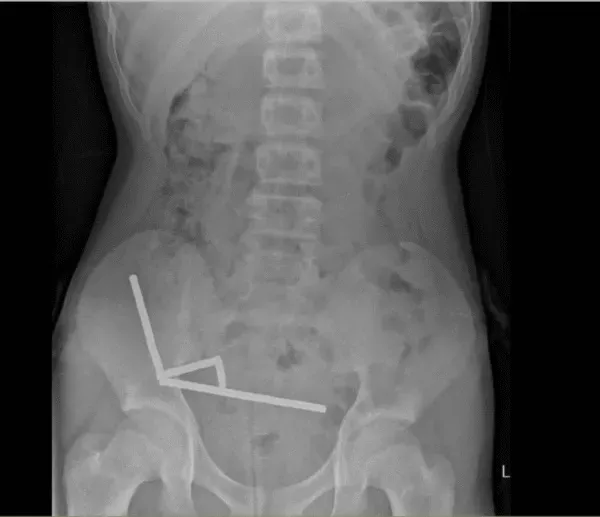

医生通过 X 光片观察到,男孩肠道的不同部位出现了四条线状的磁铁链。

手术中发现,这些磁铁链分别位于小肠不同区段及盲肠内。它们相互挤压,导致多处组织因血液供应不足而坏死,这种现象被称为压迫性坏死。

腹部 X 光片显示了磁铁分布情况 来源:Lekamalage et al.,?NZMJ, 2025